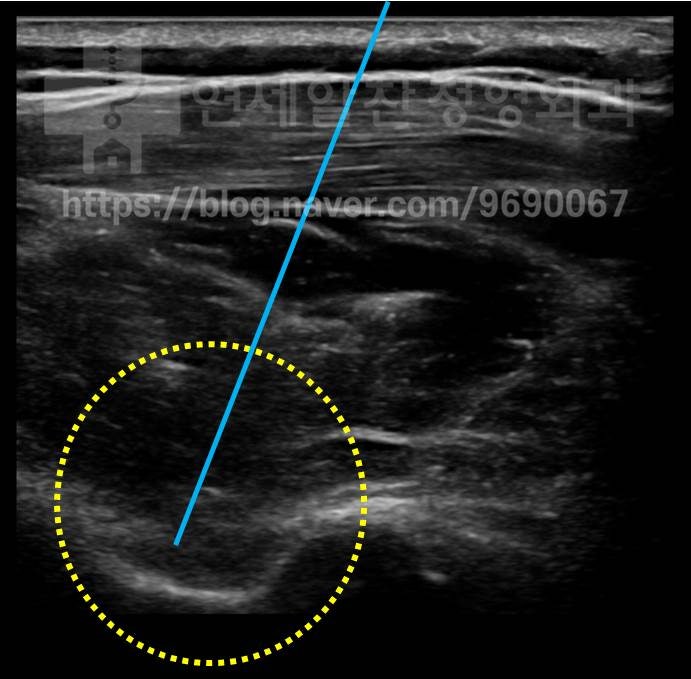

초음파로 위치를 확인한 후 주사기를 이용하여 (파란색 선) 물혹을 제거하고 난 후 앞에 보였던 물혹이 완전히 제거된 것이 관찰됩니다.

어깨 물혹을 주사기로 흡입한 사진입니다. 이 후 환자는 증상이 매우 좋아졌으며 점짐적인 재활 운동을 통해 근력도 많이 회복되었습니다. 1년 후 초음파 검사를 다시 하였습니다.